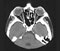

MRI of the eyeball and optic nerve CT of the eyeball and optic nerve MRI of eye muscles Review the actions of the extraocular muscles from an anterior view of the bulb.